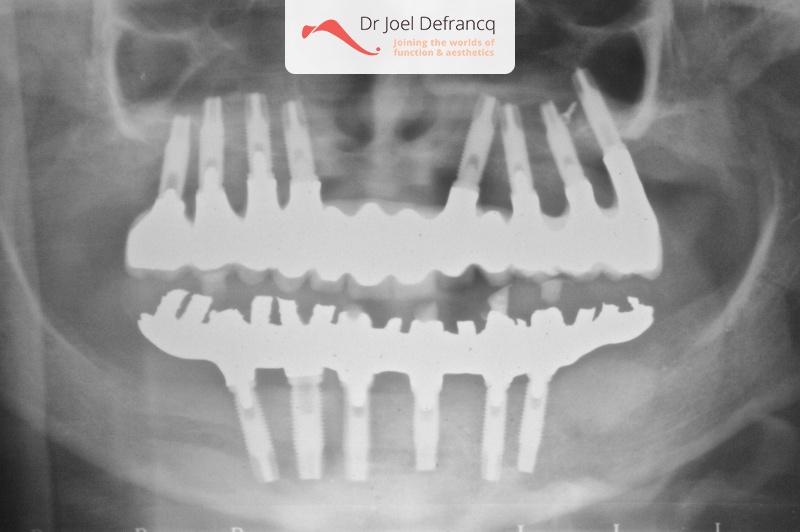

Dentale diagnose

- Open beet

Behandeling tandheelkundige implantaten

- Vaste tanden op implantaten (bovenkaak)

- Vaste tanden op implantaten (onderkaak)